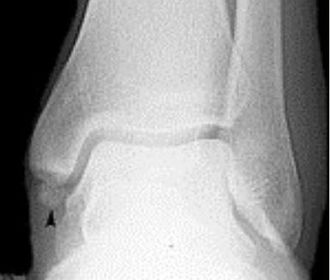

What disease is this? What does the arrow indicate? | Rheumatoid arthritis. Arrow = Bone erosion secondary to inflammation of retrocalcaneal bursa. |